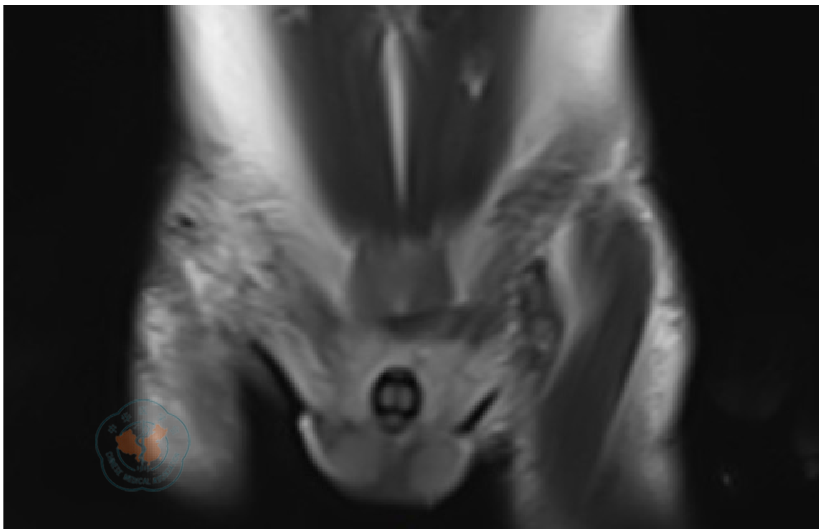

图7 阴茎癌患者术后5个月MRI检查结果注:双侧腹股沟区水肿性改变,未见肿大淋巴结